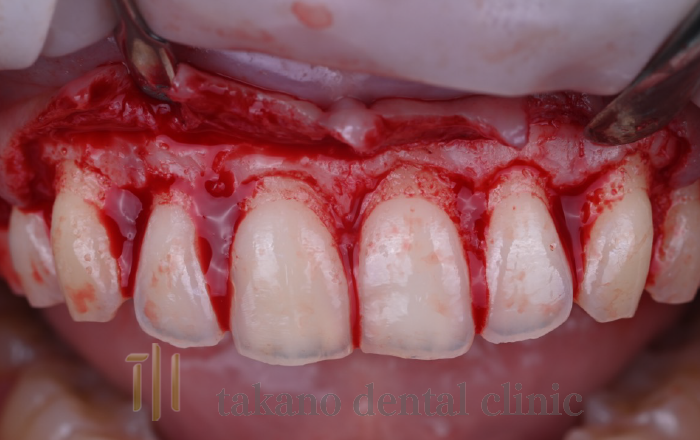

下がった歯ぐきを治療するためには歯周形成外科治療が必要になります下がった歯ぐきを治療するためには歯周形成外科治療が必要になります。外科治療には遊離歯肉移植術、結合組織移植術、歯肉弁歯冠側移動術といった手術をおこないます。

結合組織移植術

case02

• 術前

治療例

• 術中